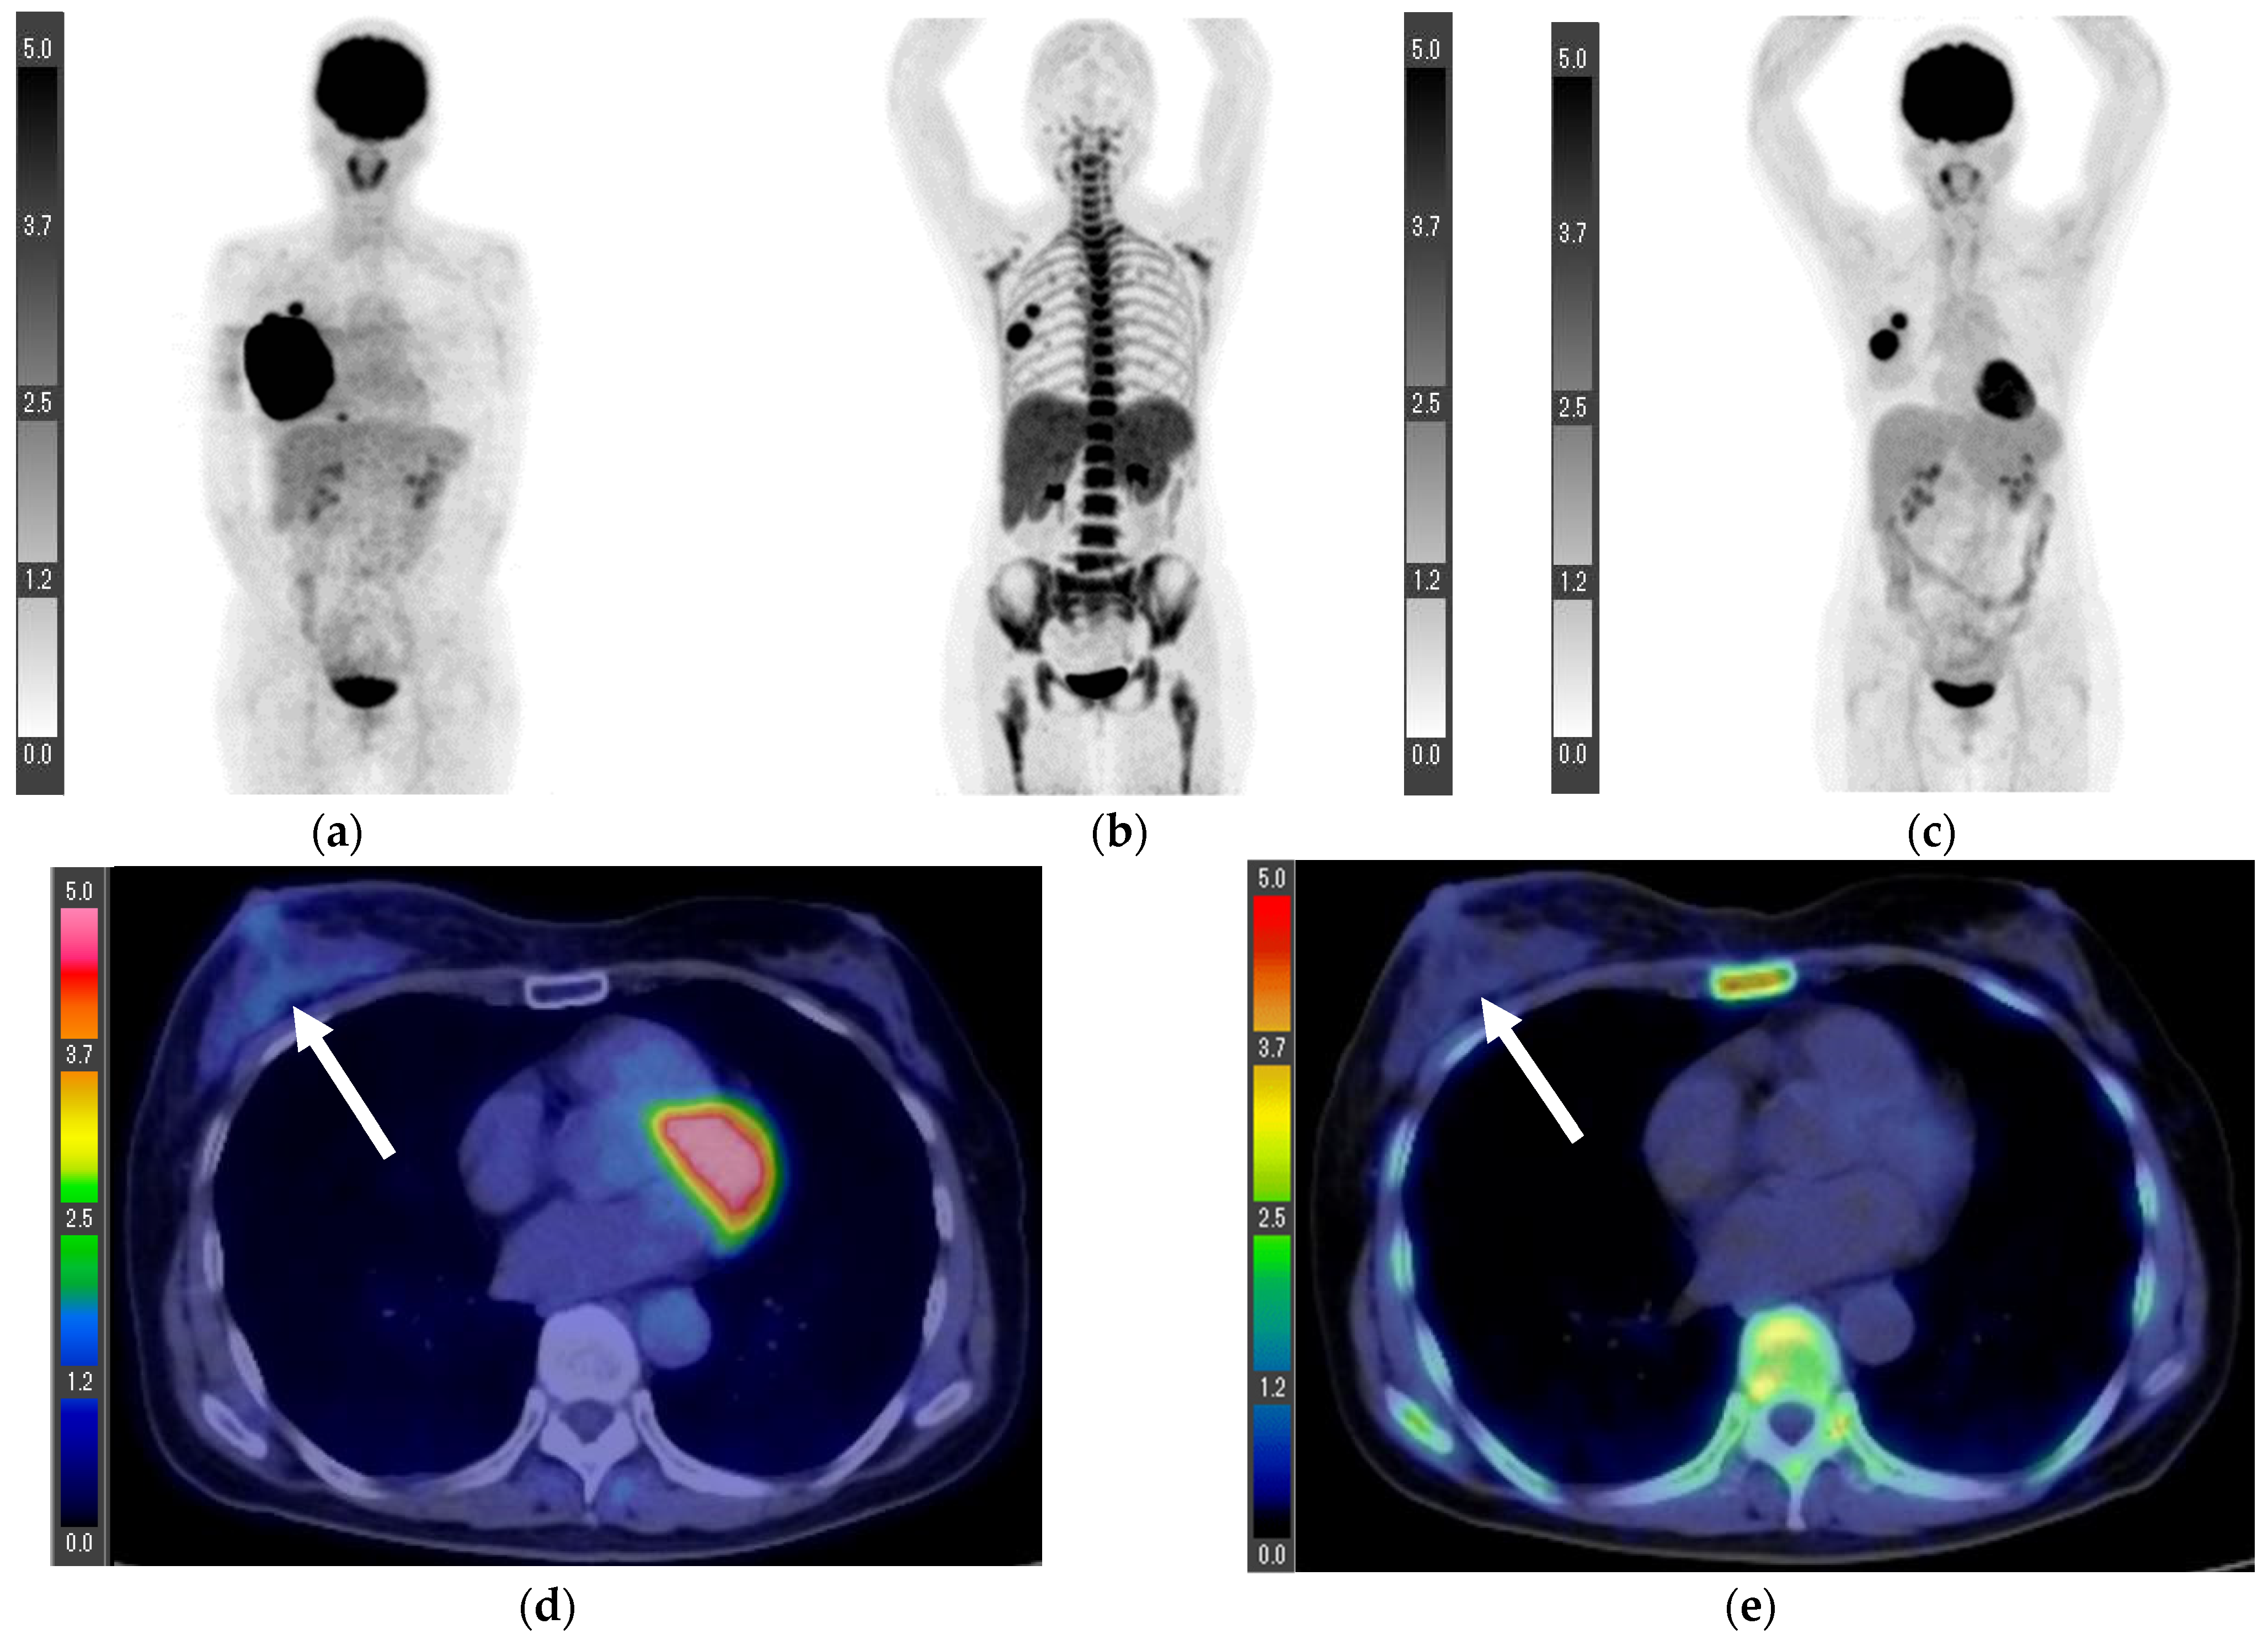

| Patient | Primary FLT | Primary FDG | LN FLT | LN FDG | Stage | Histological Diagnosis | Nuclear Grade | ER | PR | HER2 | Ki-67 (%) |

|---|---|---|---|---|---|---|---|---|---|---|---|

| 1 | 1.0 | 1.8 | 1.6 * | 3.4 * | T1cN2aM0 ** | Invasive ductal carcinoma | 1 | + | + | − | 1.0 |

| 2 | 0.6 | 1.6 | 0.7 | 0.8 | T1bN0M0 ** | Invasive ductal carcinoma | 1 | + | + | − | 6.7 |

| 3 | 2.2 | 3.1 | 0.5 | 0.6 | T1cN0M0 ** | Invasive ductal carcinoma | 2 | + | + | − | 24.6 |

| 4 | 0.4 | 1.5 | 16.7 * | 14.2 * | T1bN3aM1 *** (Lymph node and bone metastases) | Invasive ductal carcinoma | Data loss | + | + | − | Data loss |

| 5 | 3.8 | 8.3 | 1.8 | 6.3 | T2N3bM0 *** | Invasive ductal carcinoma | 1 | + | + | − | 25 |

| 6 | 4.8 | 8.4 | 1.4 | 3.2 | T4bN1M1 *** (Lumbar vertebra metastasis) | Invasive ductal carcinoma | 1 | + | + | − | 8.9 |

| 7 **** | 7.0 | 10.1 | 1.2 | 0.7 | T4bN0M0 | Invasive ductal carcinoma | Data loss | − | − | + | 59 |

| 8 ***** | - | - | 1.1 | 4.1 | N3bM1 (Lymph node, lung, and bone metastases) | Invasive ductal carcinoma | 3 | + | − | + | 29.3 |